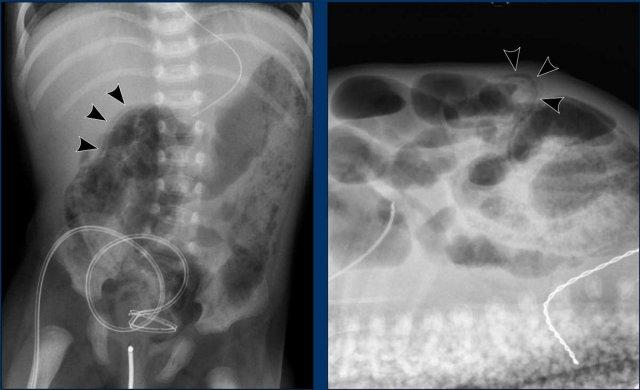

Hình ảnh

Bé trai 4 tháng tuổi đã phẫu thuật tim bẩm sinh phức tạp, hiện có phân lẫn máu.

X-quang bụng cho thấy khí trong thành ruột (pneumatosis) (mũi tên).

Dấu hiệu này cũng được thấy trên siêu âm ở đoạn ruột bên trái, trong khi đoạn ruột lành bên phải cho thấy các phản âm hơi bình thường.